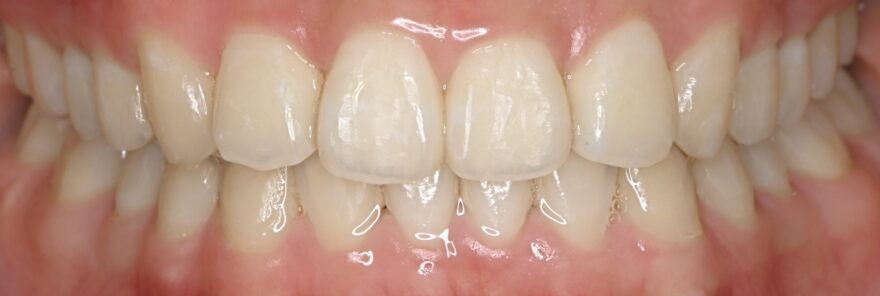

治療後の口腔内写真

約2年の動的期間(歯を動かす時期)で、ここまで整った歯並びになりました。

インビザラインでもワイヤー矯正でも、最終的な仕上がりに差はありません。

八重歯が完全に治りました。

前歯には後戻りを防止するための保定装置を装着しています。